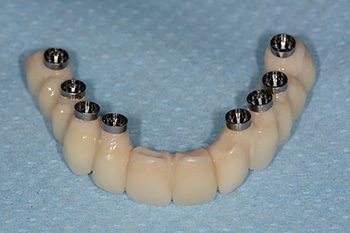

Aspect du bridge d’usage en zircone avant vissage.